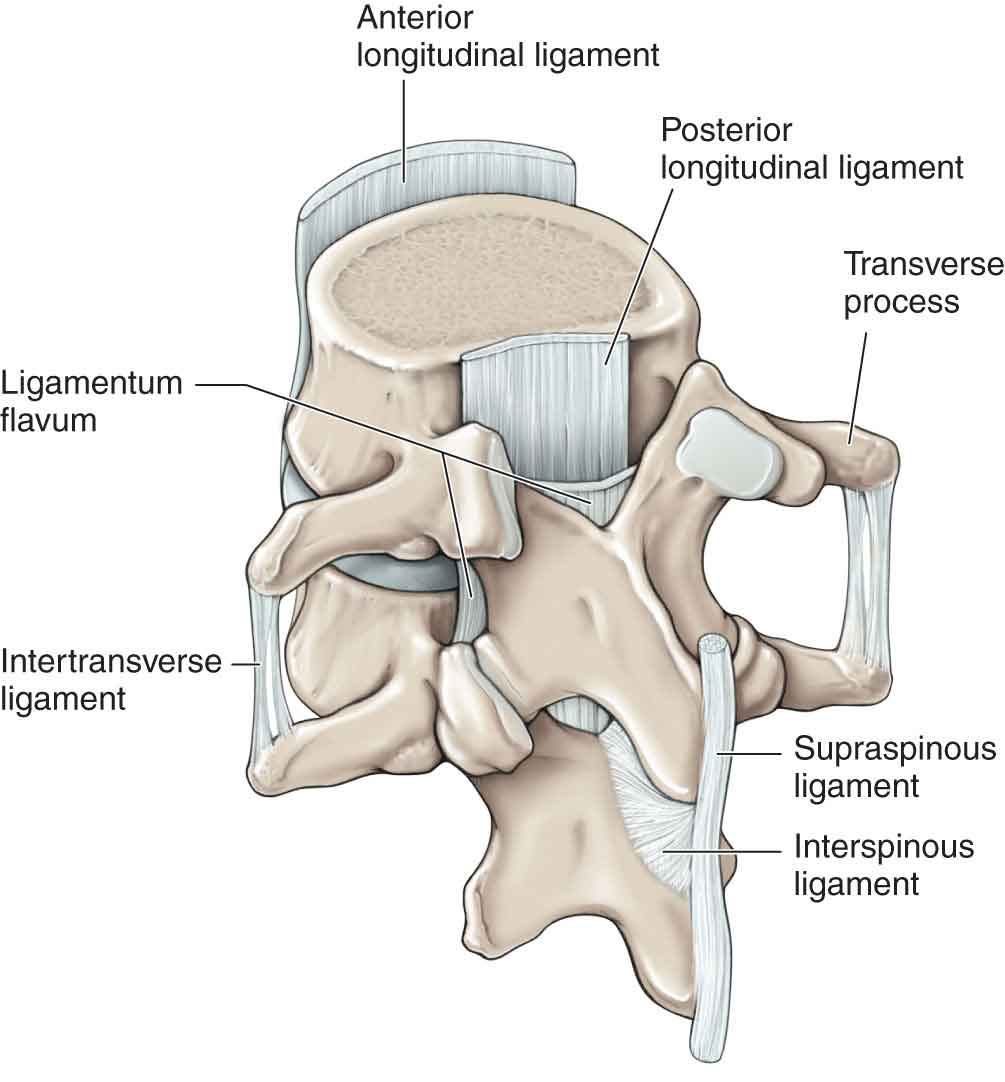

Interspinous Ligament

The Supraspinous and Interspinous Ligaments of the Lumbar Spine (circa 1978). – Husson U PT blog

Pure Health - Anatomy 101 - Supraspinous ligament and interspinous ligament 📚 The supraspinous ligament and interspinous ligament work together to limit flexion of the spine by limiting separation of the spinous

DOCS - The interspinous ligament is located between the spinous processes of adjacent vertebrae in the spine. It extends from the base of one spinous process to the apex of the next,